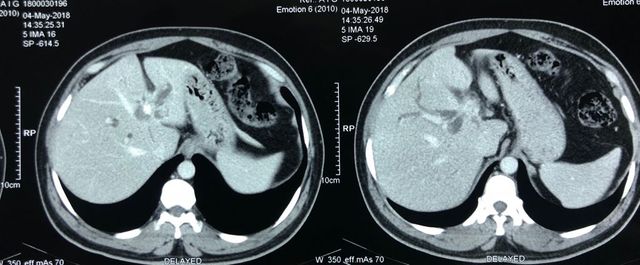

A rare case of gastric schwannoma masquerading as a GIST - 52 year old lady presented with massive GI bleed

A rare case of gastric schwannoma masquerading as a GIST. 52 year old lady presented with massive GI bleed and severe anemia Hb 5.0 gm. Her CT scan and endoscopy revealed a exophytic lesion 10 x 12 cmof gastric body with a ulceration in stomach. She underwent a lap assisted subtotal gastrectomy with a diagnosis of a GIST. Post operative immunohistochemistry revealed a gastric schwannoma. Gastric schwannoma is a very rare mesenchymal tumor arising from the nerve plexus of gastric wall . Unlike gastric GIST of this size >10 cm which are usually the rare malignant schwannoma are entirely benign with excellent long term prognosis.